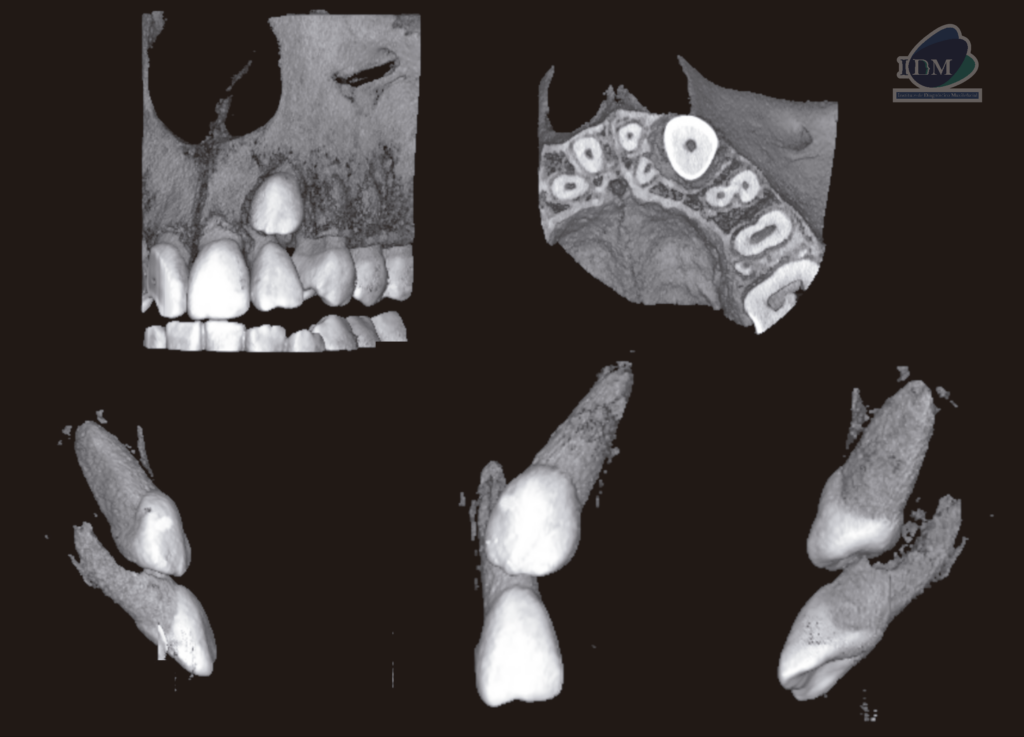

A la evaluación de la tomografía computarizada de campo reducido se observa la porción coronaria de la pieza 23 orientada hacia vestibular y ocasionando el desplazamiento palatino de la pieza 22 así como la reabsorción radicular externa vestibulodistal del tercio medio que también compromete conducto pulpar. Finalmente se observa el tercio apical de la pieza 23 en formación y en contacto con el piso de fosa nasal y seno maxilar.

RECONSTRUCCIÓN 3D